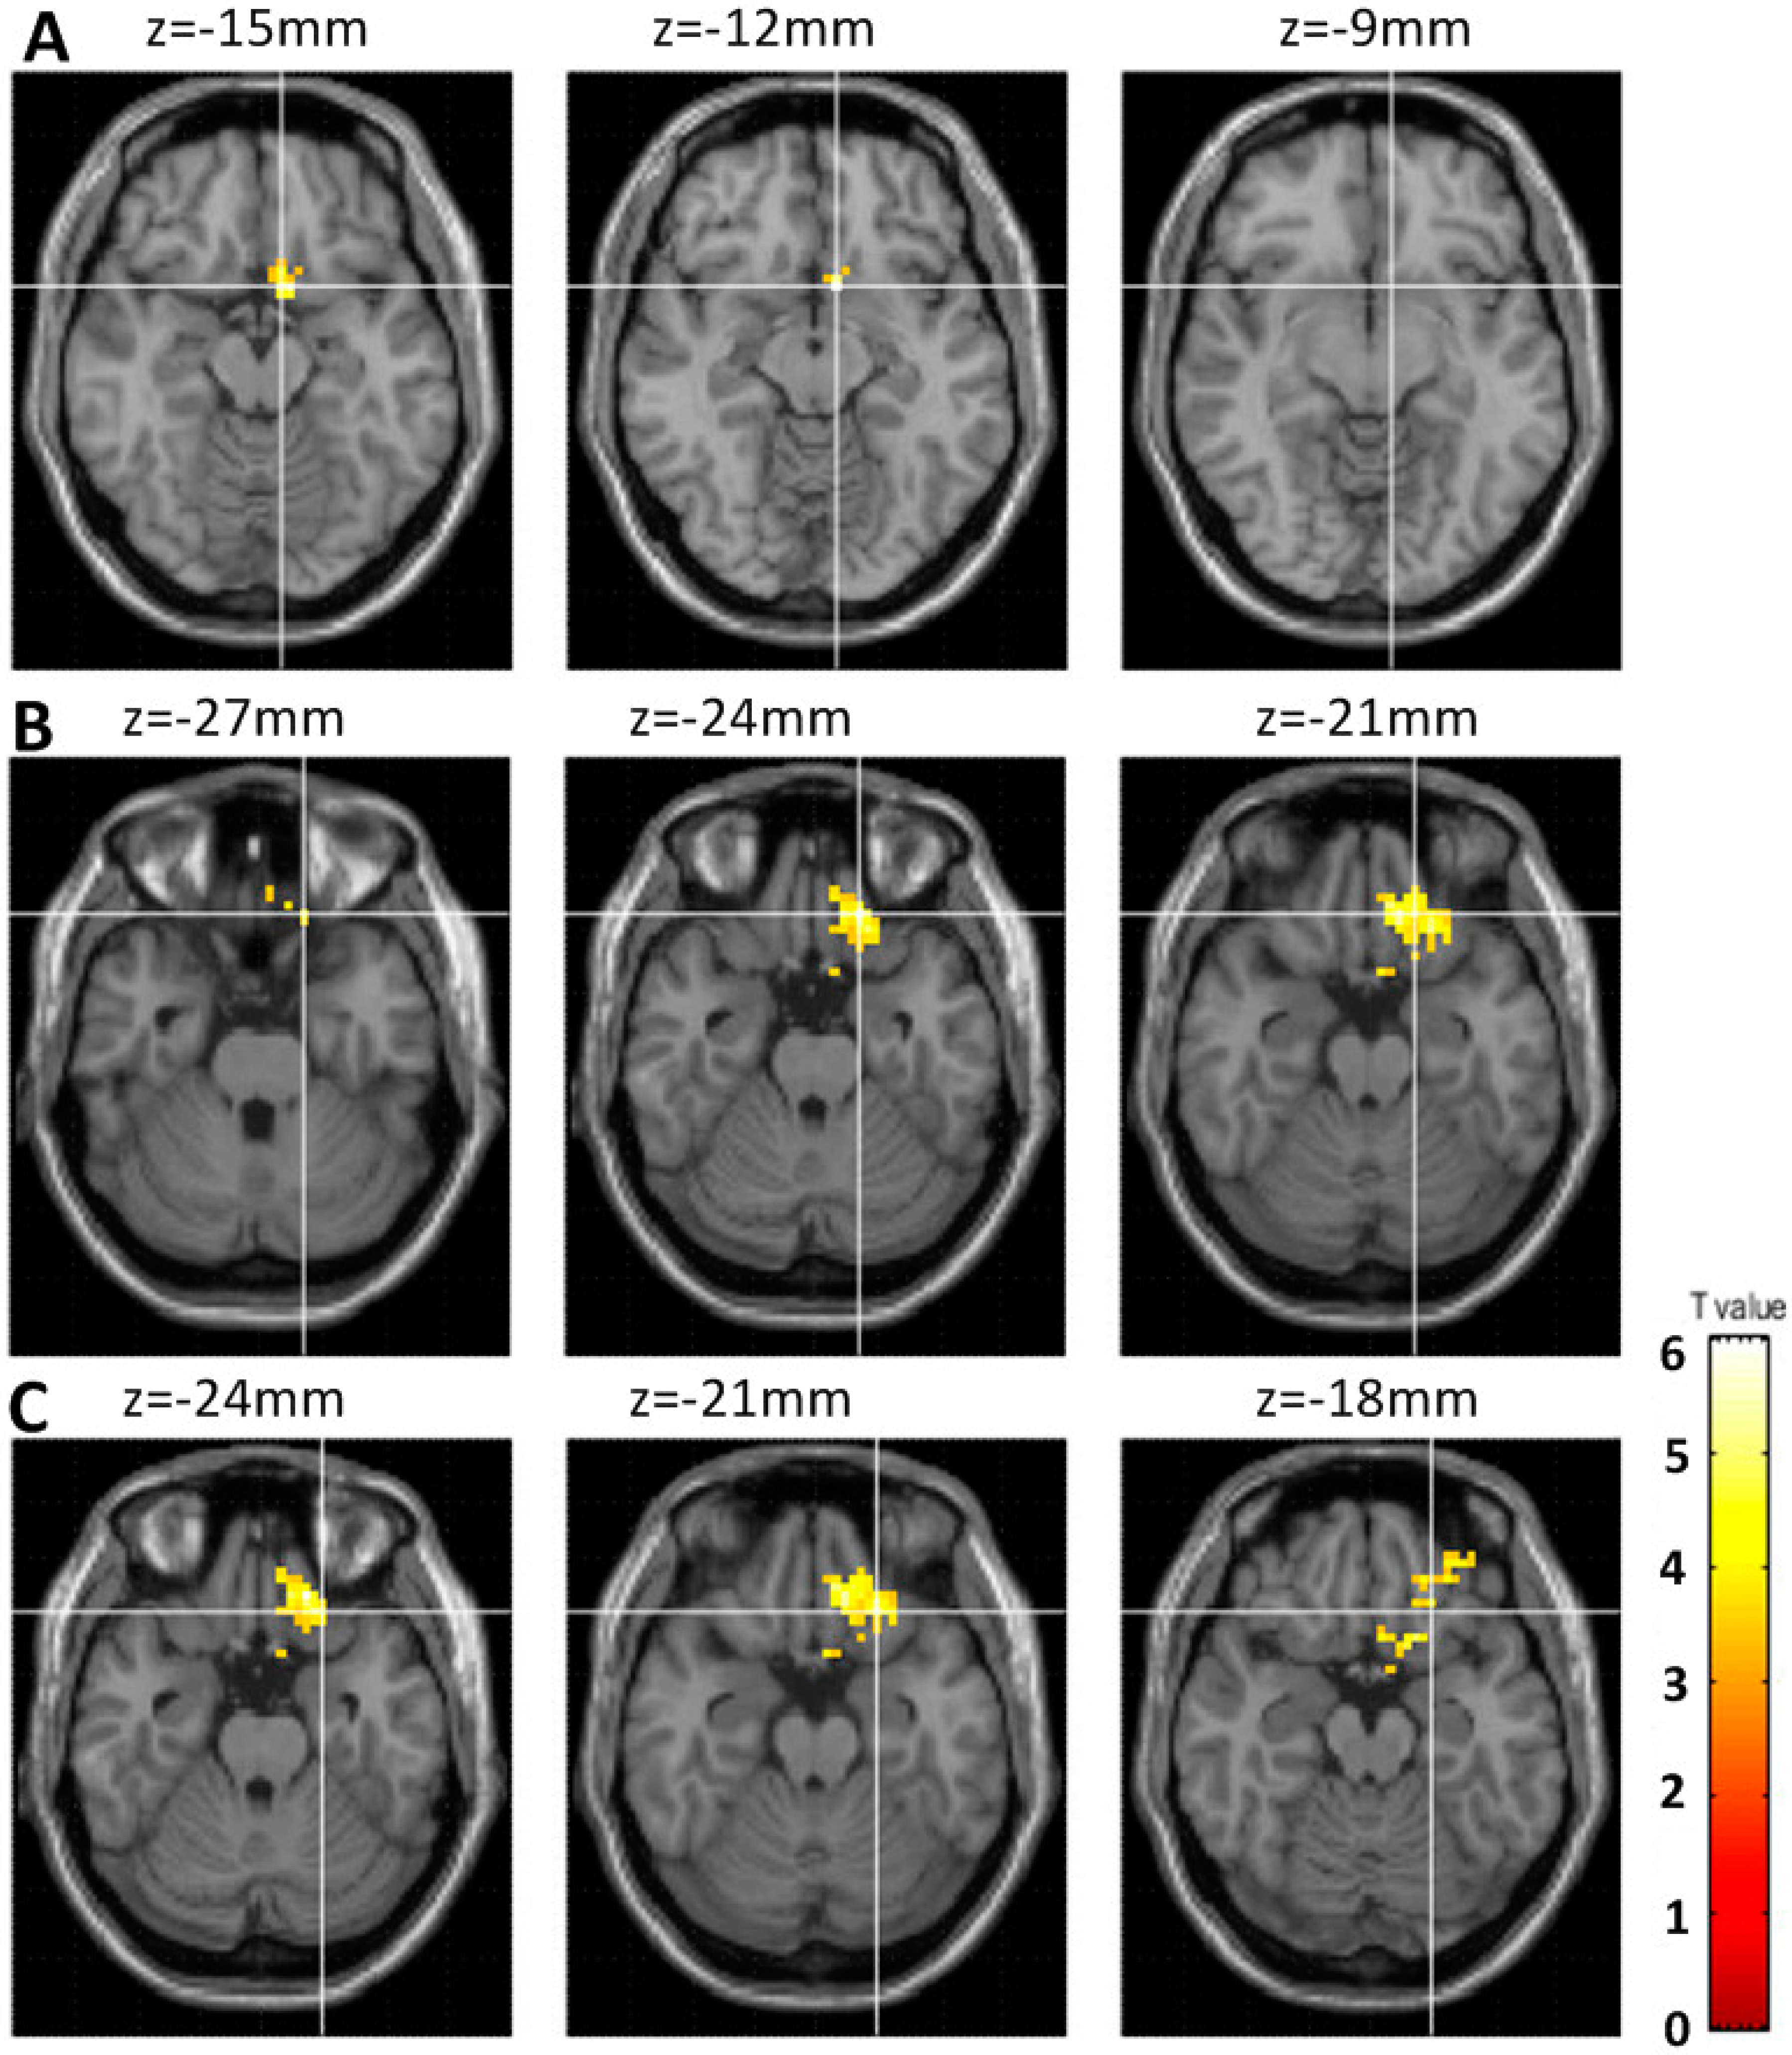

3.2. Comparison of the Changes in fALFF between Student Pro-Gamers and IGD Adolescents after a Year

4.2. Increased Brain Activity within the Attention Network (parietal lobe) in Response to One-Year Internet Gameplay in Both Groups

4.3. Increased Brain Activity within the Orbitofrontal Cortex of the IGD Adolescents in Response to a Year of Internet Gaming